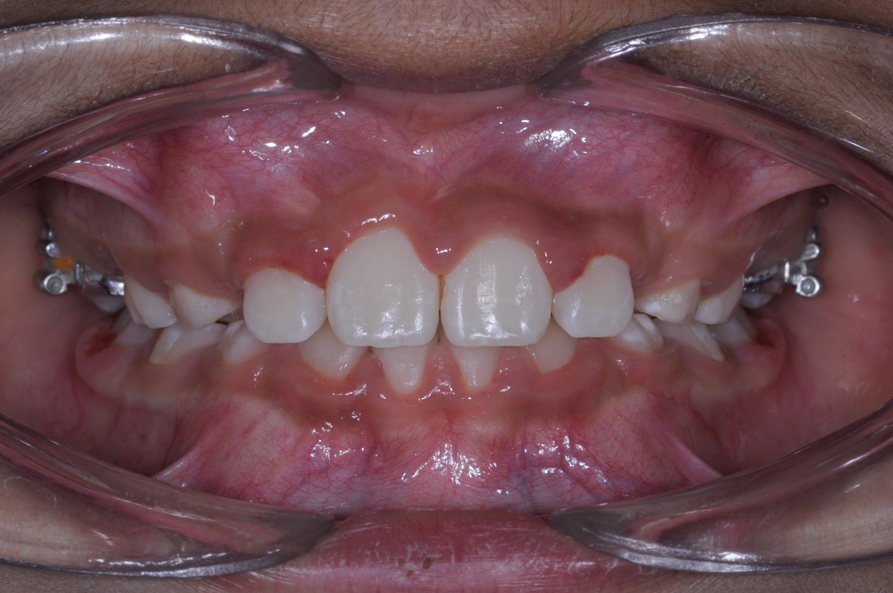

The following case illustrates the complete surgical/orthodontic treatment sequence for an impacted maxillary right central incisor. An 8½-year-old patient presented with a chief complaint of crowded teeth. The maxillary left central incisor was the only erupted incisor at the time of consultation (Figure 2 and Figure 3). Crowding was clinically diagnosed visually by the prominence of the unerupted right central incisor in the vestibule, and this was confirmed with a panoramic radiograph (Figure 4).

The maxillary right permanent centralincisor had a delayed eruption of 1½ years compared to its homologous incisor, and it was anteriorly displaced due to insufficient space in the premaxilla. Removal of the maxillary deciduous canines was indicated to unravel the crowding. An apically positioned flap of the impacted right central incisor was made to facilitate its eruption (Figure 5 and Figure 6). The case was worked up to plan an active phase l treatment, consisting of palatal expansion and the use of sectional fixed appliances in the upper arch. A transverse deficiency without posterior crossbite was identified, and therefore palatal expansion with a bonded expander was planned to widen the premaxilla (Figure 7 and Figure 8). A two-by-four fixed appliance system (brackets in the four maxillary anterior teeth and bands on the maxillary first molars) was used to align the maxillary teeth. The gingival margin of the retained maxillary right central incisor was slightly more apical than the left one, which erupted as expected (Figure 9 and Figure 10). Figure 11 shows a panoramic radiograph taken after completion of phase 1 treatment.

Fig 7. Clinical situation after rapid palatal expansion and orthodontic traction, frontal view (Fig 7) and occlusal view (Fig 8).

Figure 7

Fig 8. Clinical situation after rapid palatal expansion and orthodontic traction, frontal view (Fig 7) and occlusal view (Fig 8).

Figure 8

Fig 9. Clinical situation after completion of phase 1 treatment that allowed the impacted maxillary right central incisor to be properly positioned in the arch, frontal view (Fig 9) and occlusal view (Fig 10).

Figure 9

Fig 10. Clinical situation after completion of phase 1 treatment that allowed the impacted maxillary right central incisor to be properly positioned in the arch, frontal view (Fig 9) and occlusal view (Fig 10).

Figure 10